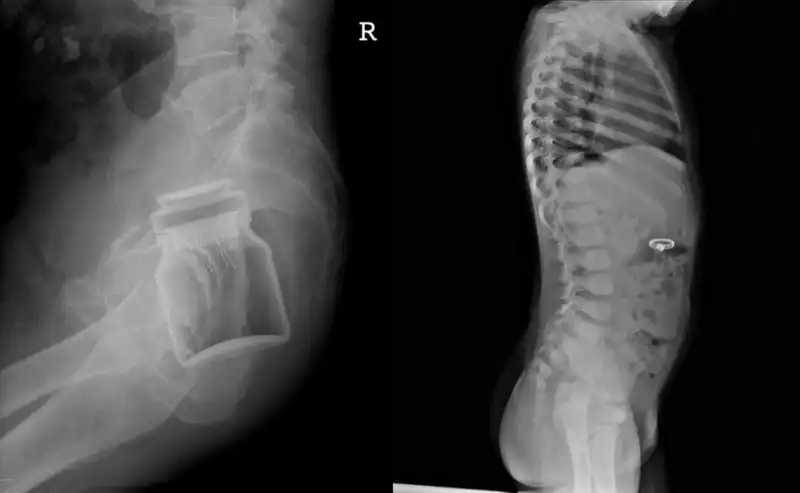

Продолжение